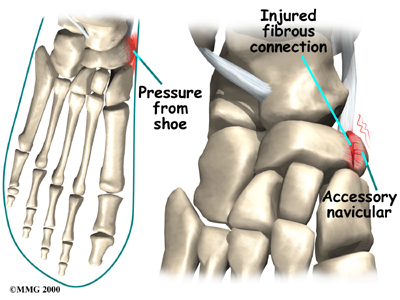

Just having an accessory navicular bone is not necessarily a bad thing. Not all people with these accessory bones have symptoms. Symptoms arise when the accessory navicular is overly large or when an injury disrupts the fibrous tissue between the navicular and the accessory navicular. A very large accessory navicular can cause a bump on the instep that rubs on your shoe causing pain.

An injury to the fibrous tissue connecting the two bones can cause something similar to a fracture. The injury allows movement to occur between the navicular and the accessory bone and is thought to be the cause of pain. The fibrous tissue is prone to poor healing and may continue to cause pain. Because the posterior tibial tendon attaches to the accessory navicular, it constantly pulls on the bone, creating even more motion between the fragments with each step.